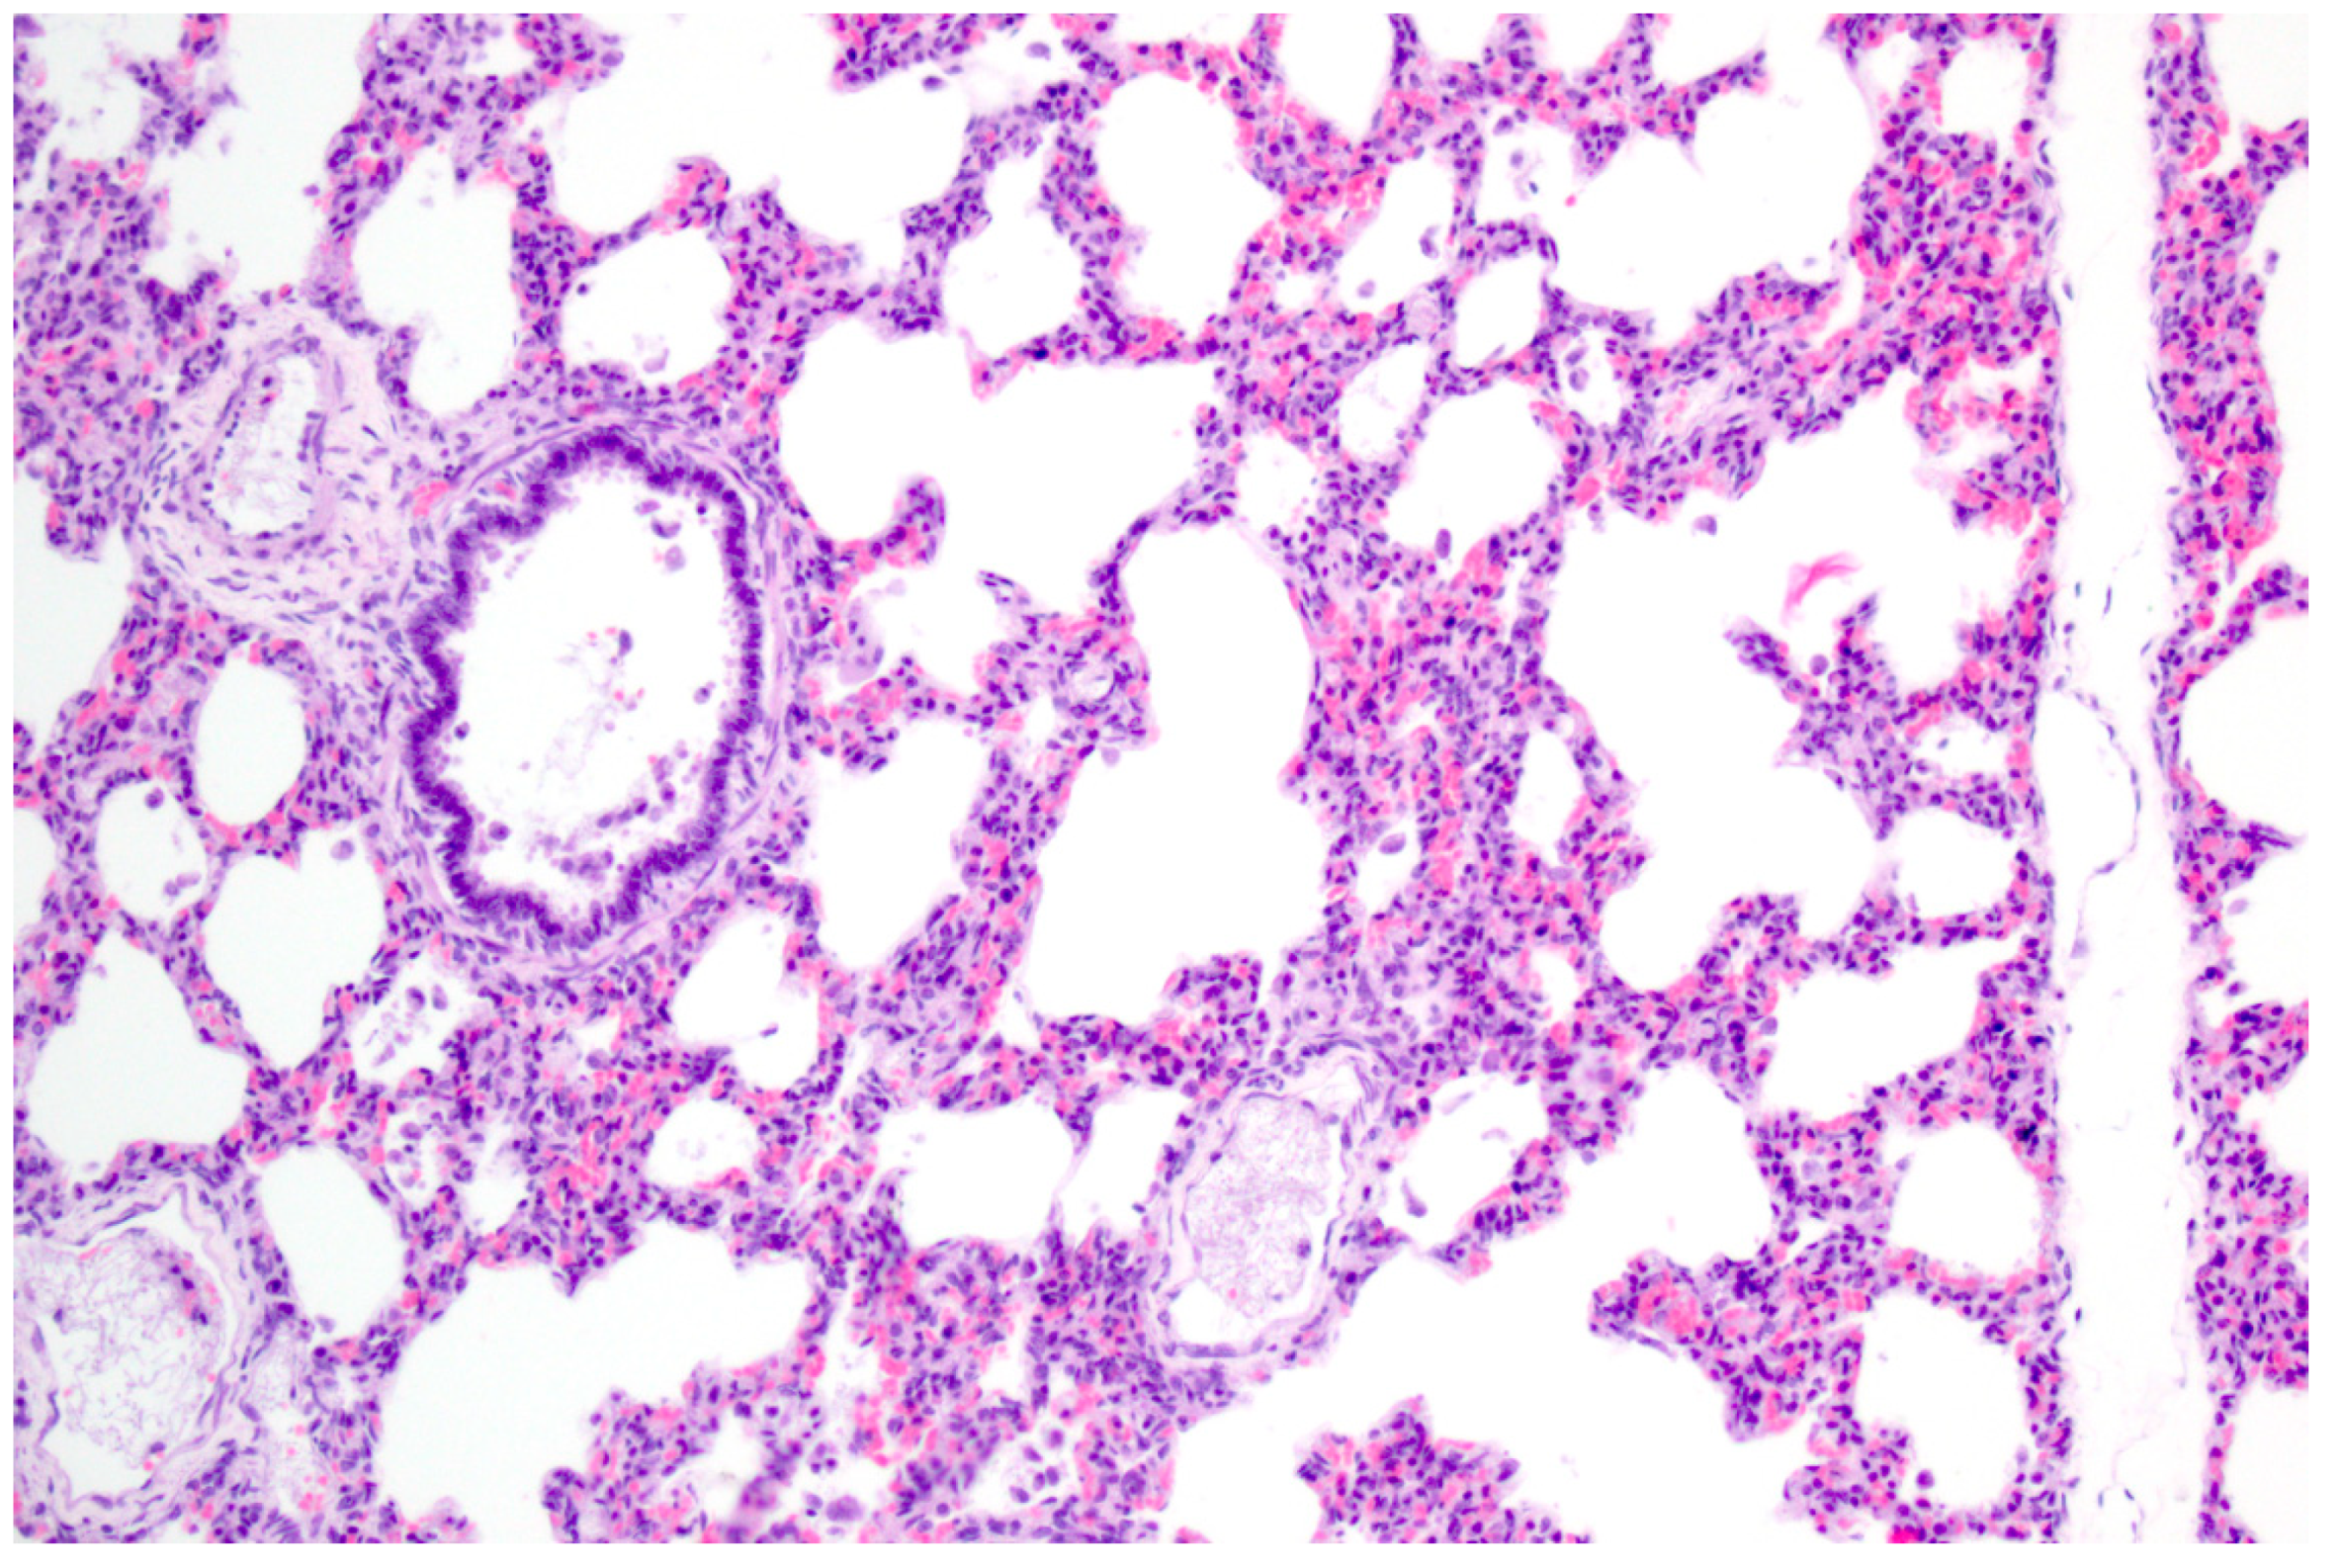

PRV is pantropic which becomes obvious microscopically. Epitheliotropic lesions appear mainly in young or aborted piglets. Multifocal necrosis occurs in the liver, spleen, tonsil, lymph node, nose, lung, adrenal gland, placenta, testicle, stomach and intestine, and is often accompanied by variable numbers of amphophilic intranuclear inclusion bodies [28,38,43,44,47,52]. Hemorrhages can be present in the lymph node [28]. In some cases of naturally infected wild boar and domestic pigs either depletion or hyperplasia of lymphoid tissue is described [28,36]. Lung lesions can be either mild or severe and range from edema to interstitial pneumonia with necrosis of the epithelium, endothelium and connective tissue [34,43,47] (Figure 3). A necrotizing inflammation of arteries, veins and lymphatic vessels accompanied by thrombosis has been described after natural infection [28,38].

Figure 3.

Interstitial pneumonia of a pig after natural PRV infection. The alveolar septa are slightly thickened with lymphohistiocytic infiltration. H.E. (Courtesy: Institute of Veterinary Pathology, Leipzig University, Leipzig).